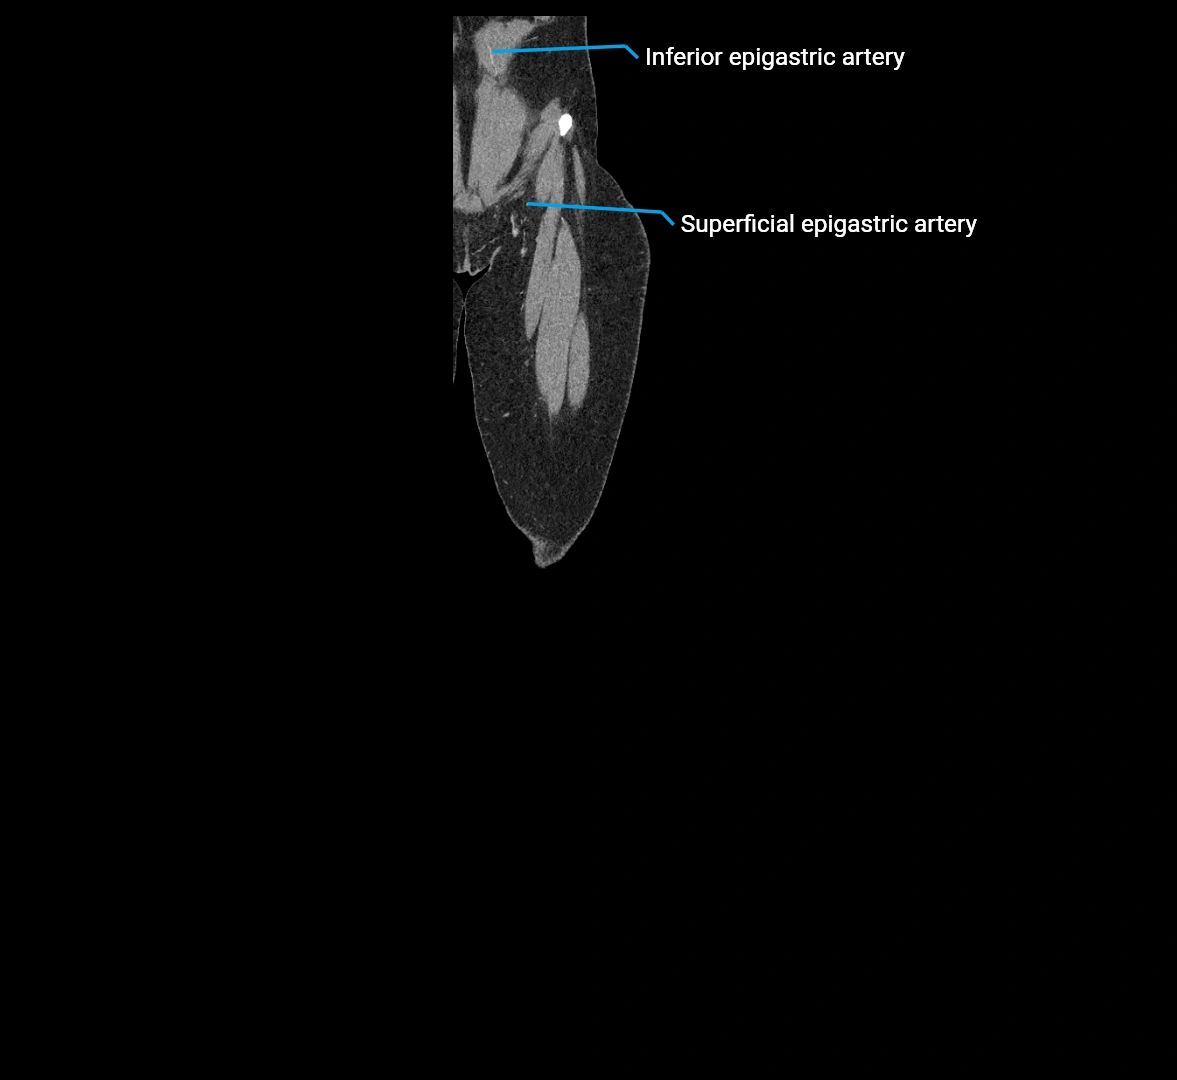

MRI images

image